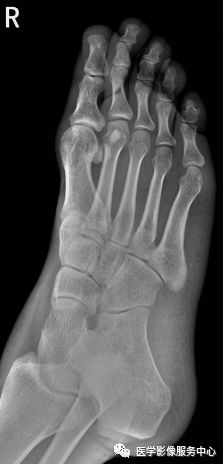

踝关节

图片

右侧外踝骨皮质连续中断,可见透亮骨折线影,可见软组织稍肿胀影。右踝关节骨折。

Warmreminder: 踝关节扭伤,许多大夫只做踝关节正侧位。有时踝关节正侧位不能看出有明显异常,而有局部软组织肿胀,活动受限时,根据我的经验,踝关节扭伤有时只做正侧位是有局限性的;小妙招足正位也是必不可少的。

此患者就是踝关节扭伤,踝关节正侧位未见异常,加拍足正位时发现外踝骨折。

所示右侧腓骨远端见斜行骨折线,骨折端对位对线尚可。右腓骨远端骨折。